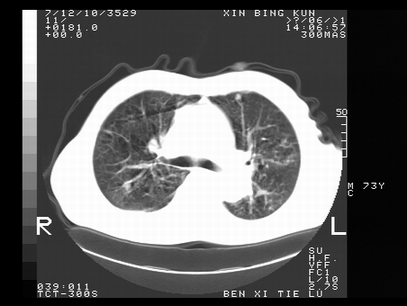

标题: CT10820:男,73岁,病史肺TB,现病史肺炎,直肠CA术后 [打印本页]

标题: CT10820:男,73岁,病史肺TB,现病史肺炎,直肠CA术后

1.两肺结核.2.两肺多发转移瘤.3右侧少量胸腔积液4.主动脉钙化.

双肺多发结节及条片状致密影,右侧少量胸腔积液。临床:直肠ca术后,肺tb病史。综合考虑:1 双肺转移!2 继发性肺结核合并感染!

两肺多发结节影,并见滋养动脉与其相连,考虑 两肺转移. 右侧胸腔积液考虑胸膜转移.

左肺上叶下叶背段,右肺中下叶见多发斑片状、条索状高密度影,兵变周围小结节影形成“树芽”样改变。 左肺上叶舌段近前胸壁处及右肺中叶内侧段见结节影。右侧胸膜腔内见液体密度区。纵隔内未见明确增大淋巴结。考虑左肺上叶舌段近前胸壁处及右肺中叶转移瘤可能性大。两肺继发型肺结核。右侧胸腔积液。

还有心包少量积液。